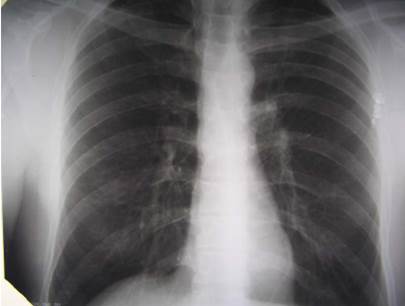

За допомогою якого методу візуалізації було отримано зазначений рисунок?